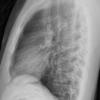

Normal  lateral

24 yo male

Date: 06/08/2016

Views: 5441